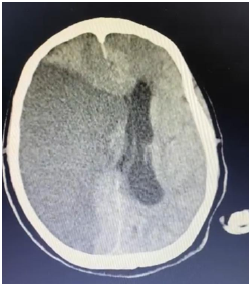

Um paciente de 76 anos de idade deu entrada na UPA, já fora de janela para trombólise, e foi posteriormente encaminhado para a UTI. A imagem apresentada refere-se à tomografia de admissão na UTI.

O paciente evoluiu com morte encefálica. O primeiro exame clínico confirmatório foi realizado às 12 horas, o segundo às 13 horas, e o método gráfico às 23 horas. Sabendo que todos os trâmites legais foram feitos, como notificação compulsória e acompanhamento com a ajuda da comissão intra-hospitalar de doação de órgãos e tecidos (CIHDOTT), qual o horário do óbito e qual a medida esperada?

Enunciado 4334994-1

Supondo que o paciente tenha evoluído com a necessidade de craniectomia descompressiva, e já há mais de 5 dias sem uso de drogas sedativas ou analgésicas, qual seria o método gráfico preferencial para a confirmação da morte encefálica para o referido paciente?

Enunciado 4334993-1

Diagnosticada a hipertensão intracraniana, a conduta mais prontamente adequada seria o uso de

Enunciado 4334992-1

Na UTI, o paciente evoluiu com aumento progressivo dos níveis pressóricos e com bradicardia.

Qual seria o exame mais facilmente disponível nesse momento, para tentar estabelecer um diagnóstico?